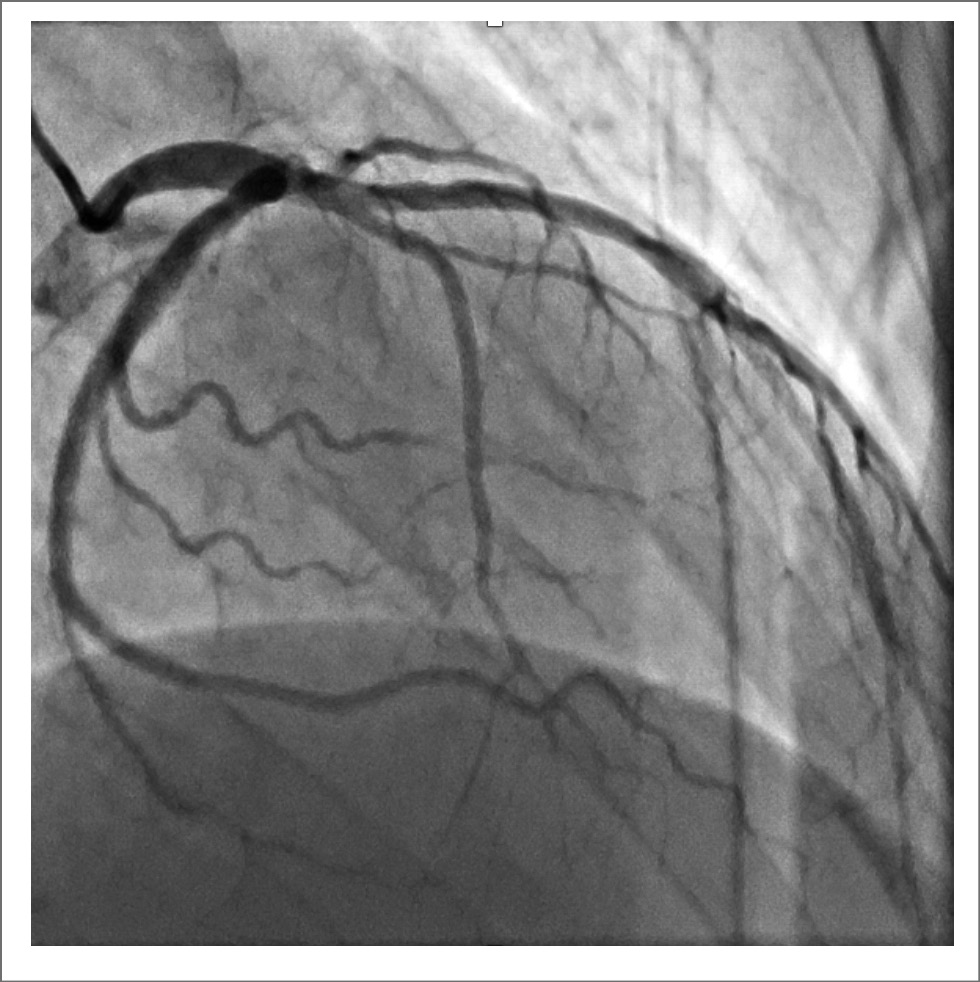

При лабораторном обследовании обращал на себя внимание лейкоцитоз до 17 тыс. со сдвигом лейкоцитарной формулы влево. Повышение уровня креатинина до 189 мкмоль/л, аланинаминотрансферазы до 3165 Ед/л, аспартатаминотрансферазы 4130 Ед/л, билирубин общий до 78 мкмоль/л, билирубин прямой до 24,5 мкмоль/л, лактатдегидрогеназа до 3700,0 Ед/л, повышение международного нормализованного отношения до 2,73. Поражение печени интерпретировано как ишемический гепатит на фоне малого сердечного выброса, в пользу чего указывало преимущественное повышение лактатдегидрогеназы по сравнению с трансаминазами. В отделении интенсивной терапии инициирована внутривенная инфузия нефракционированного гепарина под контролем активированного частичного тромбопластинового времени с переводом на ривароксабан в дозировке 30 мг/сут; диуретическая терапия. Сохранялось трепетание предсердий с тахисистолией желудочков. Попытки кардиоверсии безуспешны, аритмия тут же возобновлялась. Терапия амиодароном и β-адреноблокаторами не приводила к снижению ЧСС менее 140 уд/мин. Сохранялись относительно низкие цифры АД, менее 95/60 мм рт. ст. Тем не менее на фоне проводимой терапии состояние пациента стабилизировалось, разрешились острое почечное повреждение и ишемический гепатит. Одышка сохранялась на уровне II–III функционального класса по шкале Нью-Йоркской ассоциации сердца (NYHA). Обсуждались также ишемический, миокардитический генез ХСН. Пациенту проведена коронароангиография: коронарные артерии интактны (рис. 4).

Рис. 4. Коронароангиография: интактные коронарные артерии